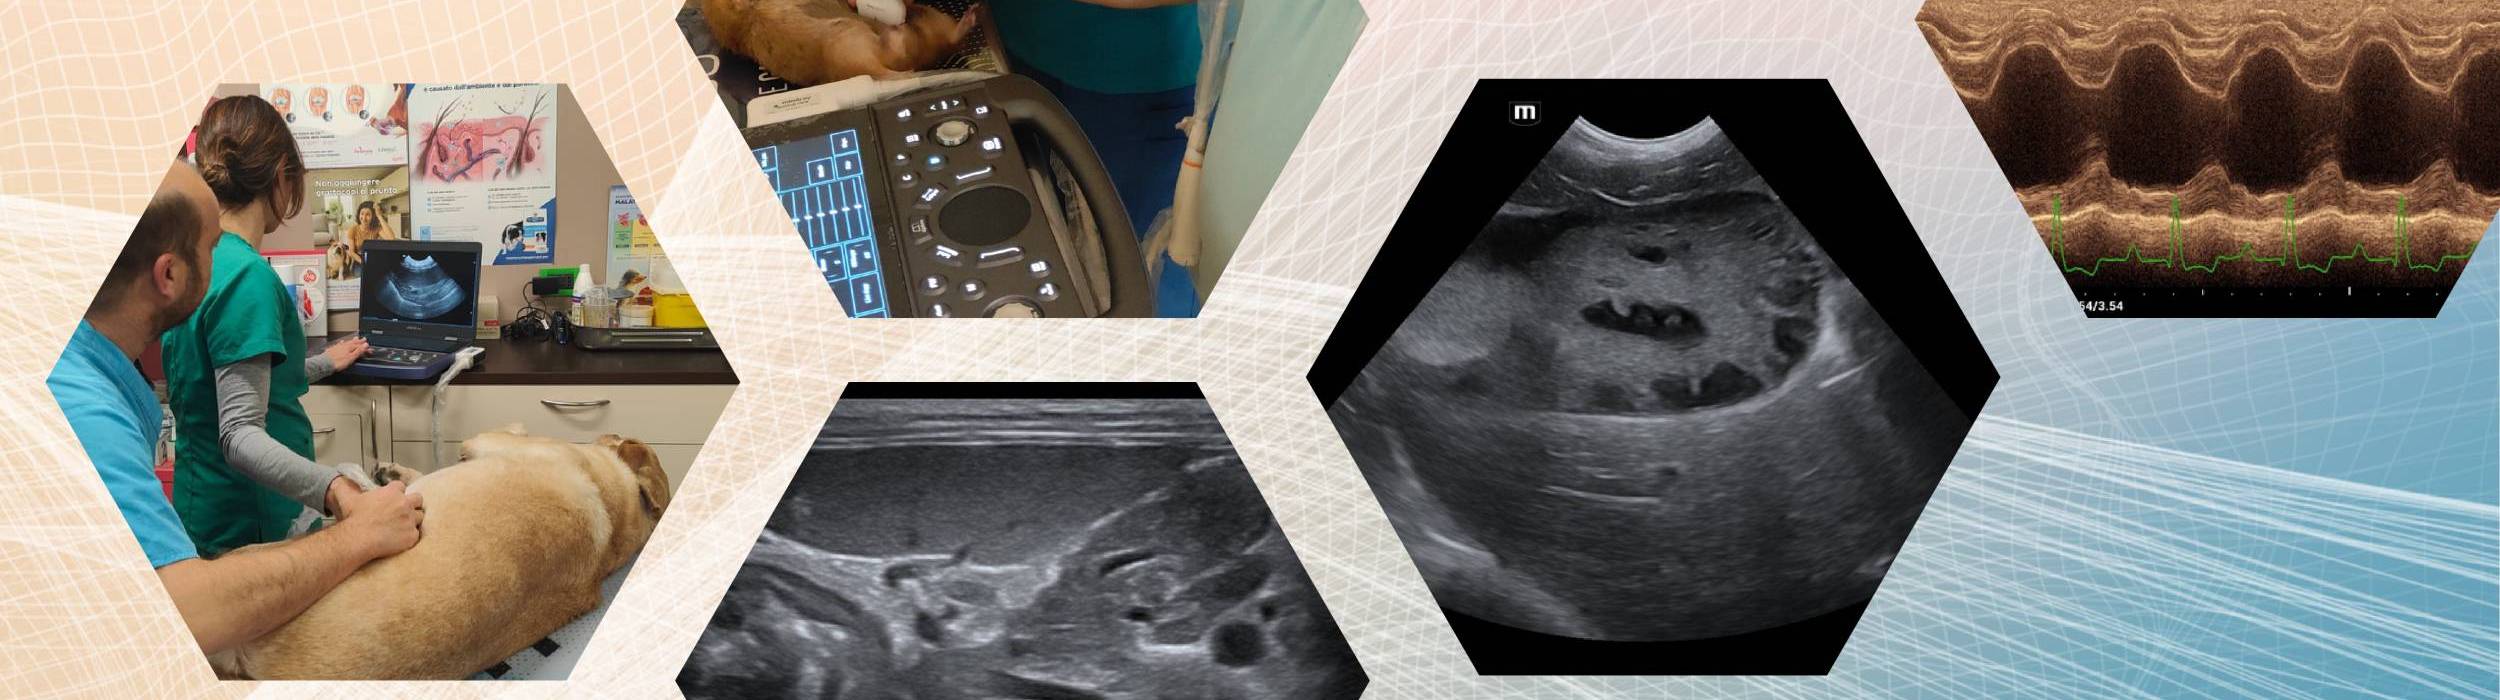

An intensive and fully tailored training experience designed to provide exclusive one-to-one mentorship, either directly with a single veterinarian or with a veterinary practice seeking structured clinical support.

The program typically runs over one or two full working days, with a strong emphasis on hands-on clinical activity and real-case application.

Individual mentorship focused on direct clinical practice in abdominal ultrasound or echocardiography, with real-time guidance and immediate feedback (single Veterinarian). - One-to-Clinic

On-site training delivered within the requesting clinic, aimed at optimizing diagnostic protocols, workflow integration, and the effective use of available ultrasound equipment.

- Abdominal ultrasound

- Basic and advanced echocardiography